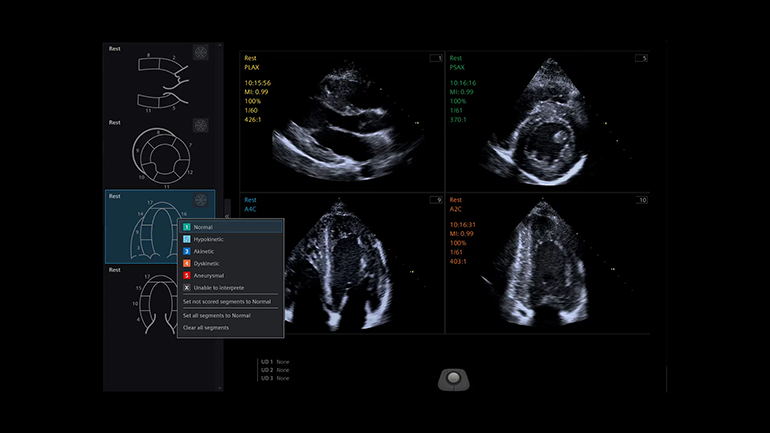

Стресс-эхокардиография. Функция стресс-эхокардиографии включает в себя комплекс инструментов и измерений для получения данных о циклах сердечной деятельности на различных этапах стресс-эхокардиографического исследования, просмотра, выборочного сравнения, оценки и архивирования наборов кинопетель с ЭКГ-синхронизацией.

Стресс-эхокардиография. Функция стресс-эхокардиографии включает в себя комплекс инструментов и измерений для получения данных о циклах сердечной деятельности на различных этапах стресс-эхокардиографического исследования, просмотра, выборочного сравнения, оценки и архивирования наборов кинопетель с ЭКГ-синхронизацией. Технология оценки скорости распространения поперечной волны и эластичности в выбранной области интереса (Virtual Touch quantification). Метод измерения скорости поперечных (сдвиговых волн) в режиме реального времени, в котором используются низкочастотные акустические импульсы (ARFI), генерируемые непосредственно ультразвуковым датчиком. Оценка скоростей сдвиговых волн в выбранной врачом зоне интереса коррелирует с показателями жесткости ткани.